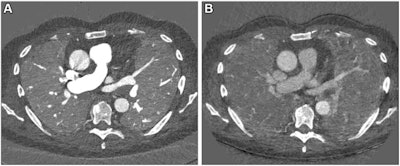

Chest CT is the gold standard for the evaluation of lung disease and for tracking disease progression, the researchers noted. But CT exams of lung function and blood flow require particular protocols that can't be combined. That's where PCCT comes in, offering high image quality, lower radiation dose compared to standard CT, better resolution, and spectral imaging options.

Scharm and colleagues developed a chest imaging protocol that produces structural and functional data from CT images with PCCT. The protocol requires advanced software but no additional equipment.

The protocol simultaneously evaluated patients' lung structure, ventilation, vasculature, and perfusion of the parenchyma, demonstrating advantages over standard CT, the team reported.